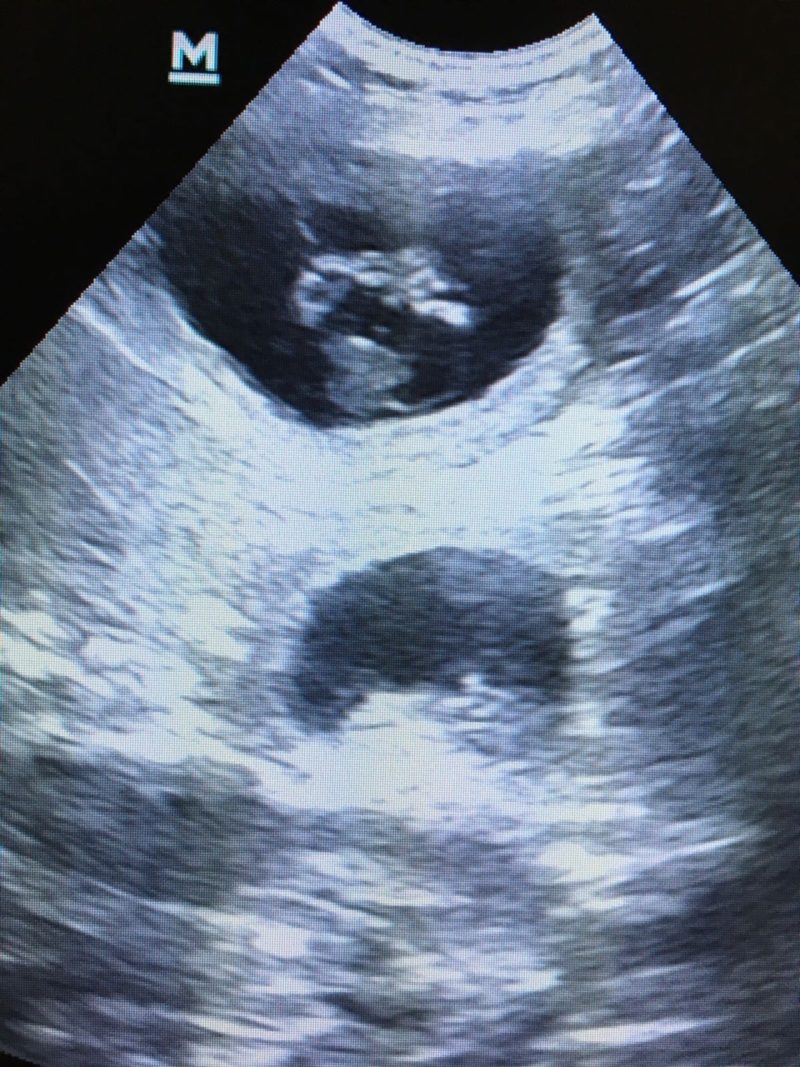

Die Besitzer von Nala, einer dreijährigen braune Labrador-Hündin, wünschten sich Welpennachwuchs. Nachdem der passende Rüde gefunden war, wurde der Wunsch Wirklichkeit. Nach ca. 28 Tagen konnte per Ultraschall eine Trächtigkeit bei Nala nachgewiesen werden.

Die Untersuchungen Nalas per Ultraschall und Röntgen ergaben keine pathologischen (krankhaften) Befunde. Bei der Blutuntersuchung wurden eine leichte Anämie (Blutarmut) und ein deutlicher Hinweis auf eine bakterielle Infektion festgestellt. Nach entsprechender medikamenteller Behandlung mit Dauertropfinfusion wurde ein Welpe geboren. Trotz sich anschließender Arzneimittelgaben konnte keine weitere Spontangeburt ausgelöst werden.